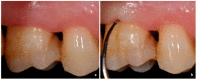

Various classification systems have been proposed to describe furcation lesions and Glickman's classification for many years seems to have been the most widely utilized in the sole clinical diagnosis with no reference to the prognostic value of the lesion itself. This article reviews the previous classification systems and proposes a new method to classify furcation lesions based on the position of the gingival margin and its relationship with the furcation area (clinically exposed/non-exposed furcation area) providing significant aid for a better understanding of furcation involvements and increases the prognostic value of treatments in the long term.